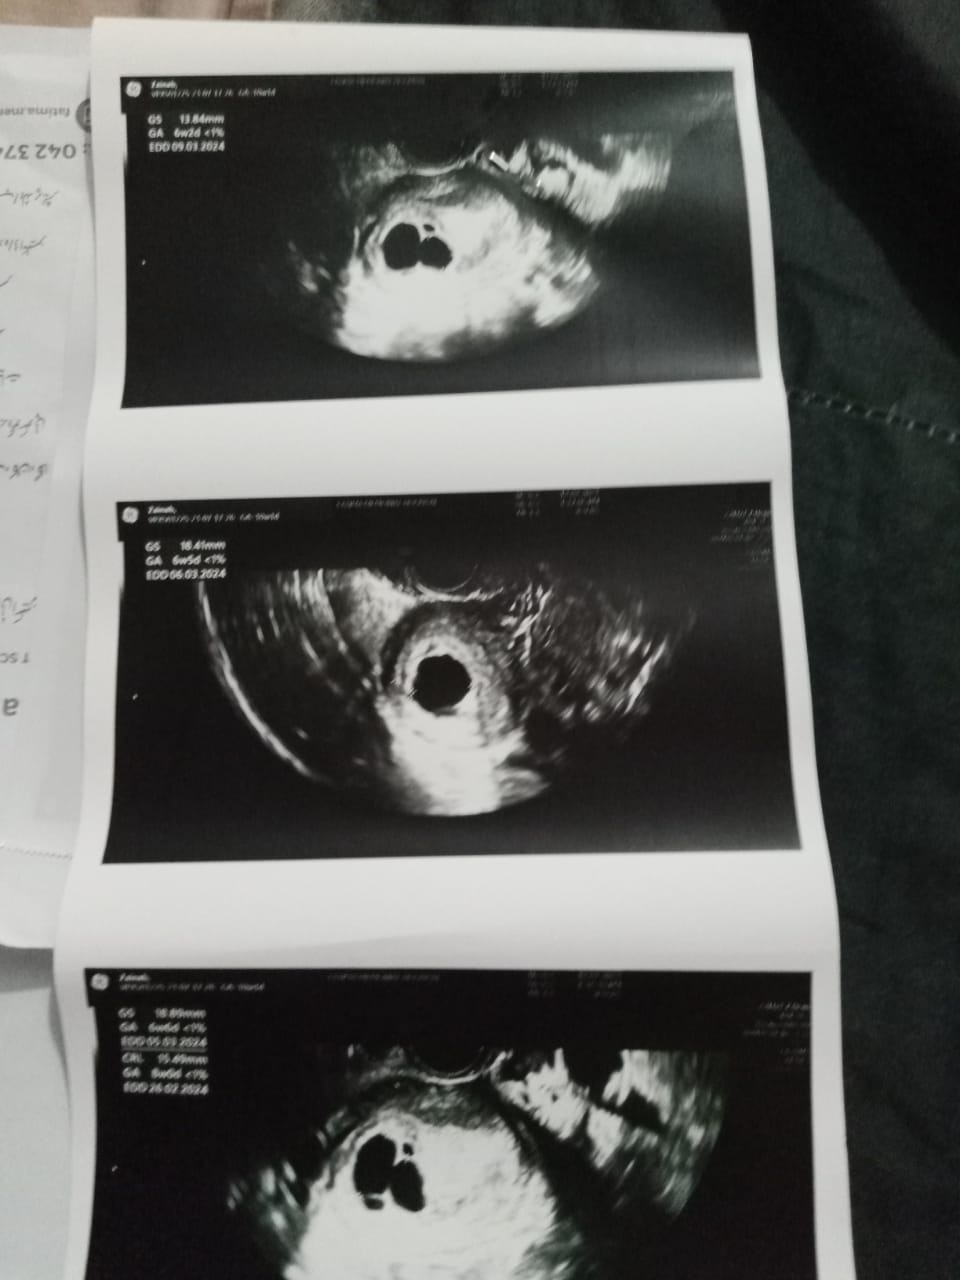

Talk to Gynecologist on There Is No Growth

is there any hope for growth as the LMP isn't remembered any suggestions? should we wait for a week or go for other procedure?

Repeat scan in 7-10 days

wait for week

You can wait if there is no bleeding , otherwise doesn't seem to be of use .

repeat ultrasound in 7 to 10 days

wait for one week than repeat TVS

Not very hopeful but you can still wait for a week. Visit in clinic if you are in lahore.